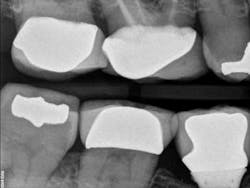

Fig. 3: Final X-ray after cementation. Temporary cement on the distal has been removed.